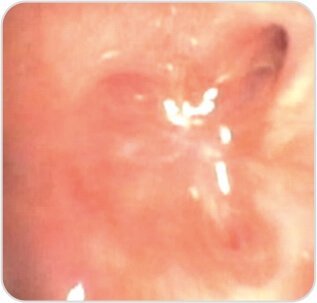

Post procedure – Luminal patency was achieved with visualization of distal segmental bronchii.

Post Procedure

After